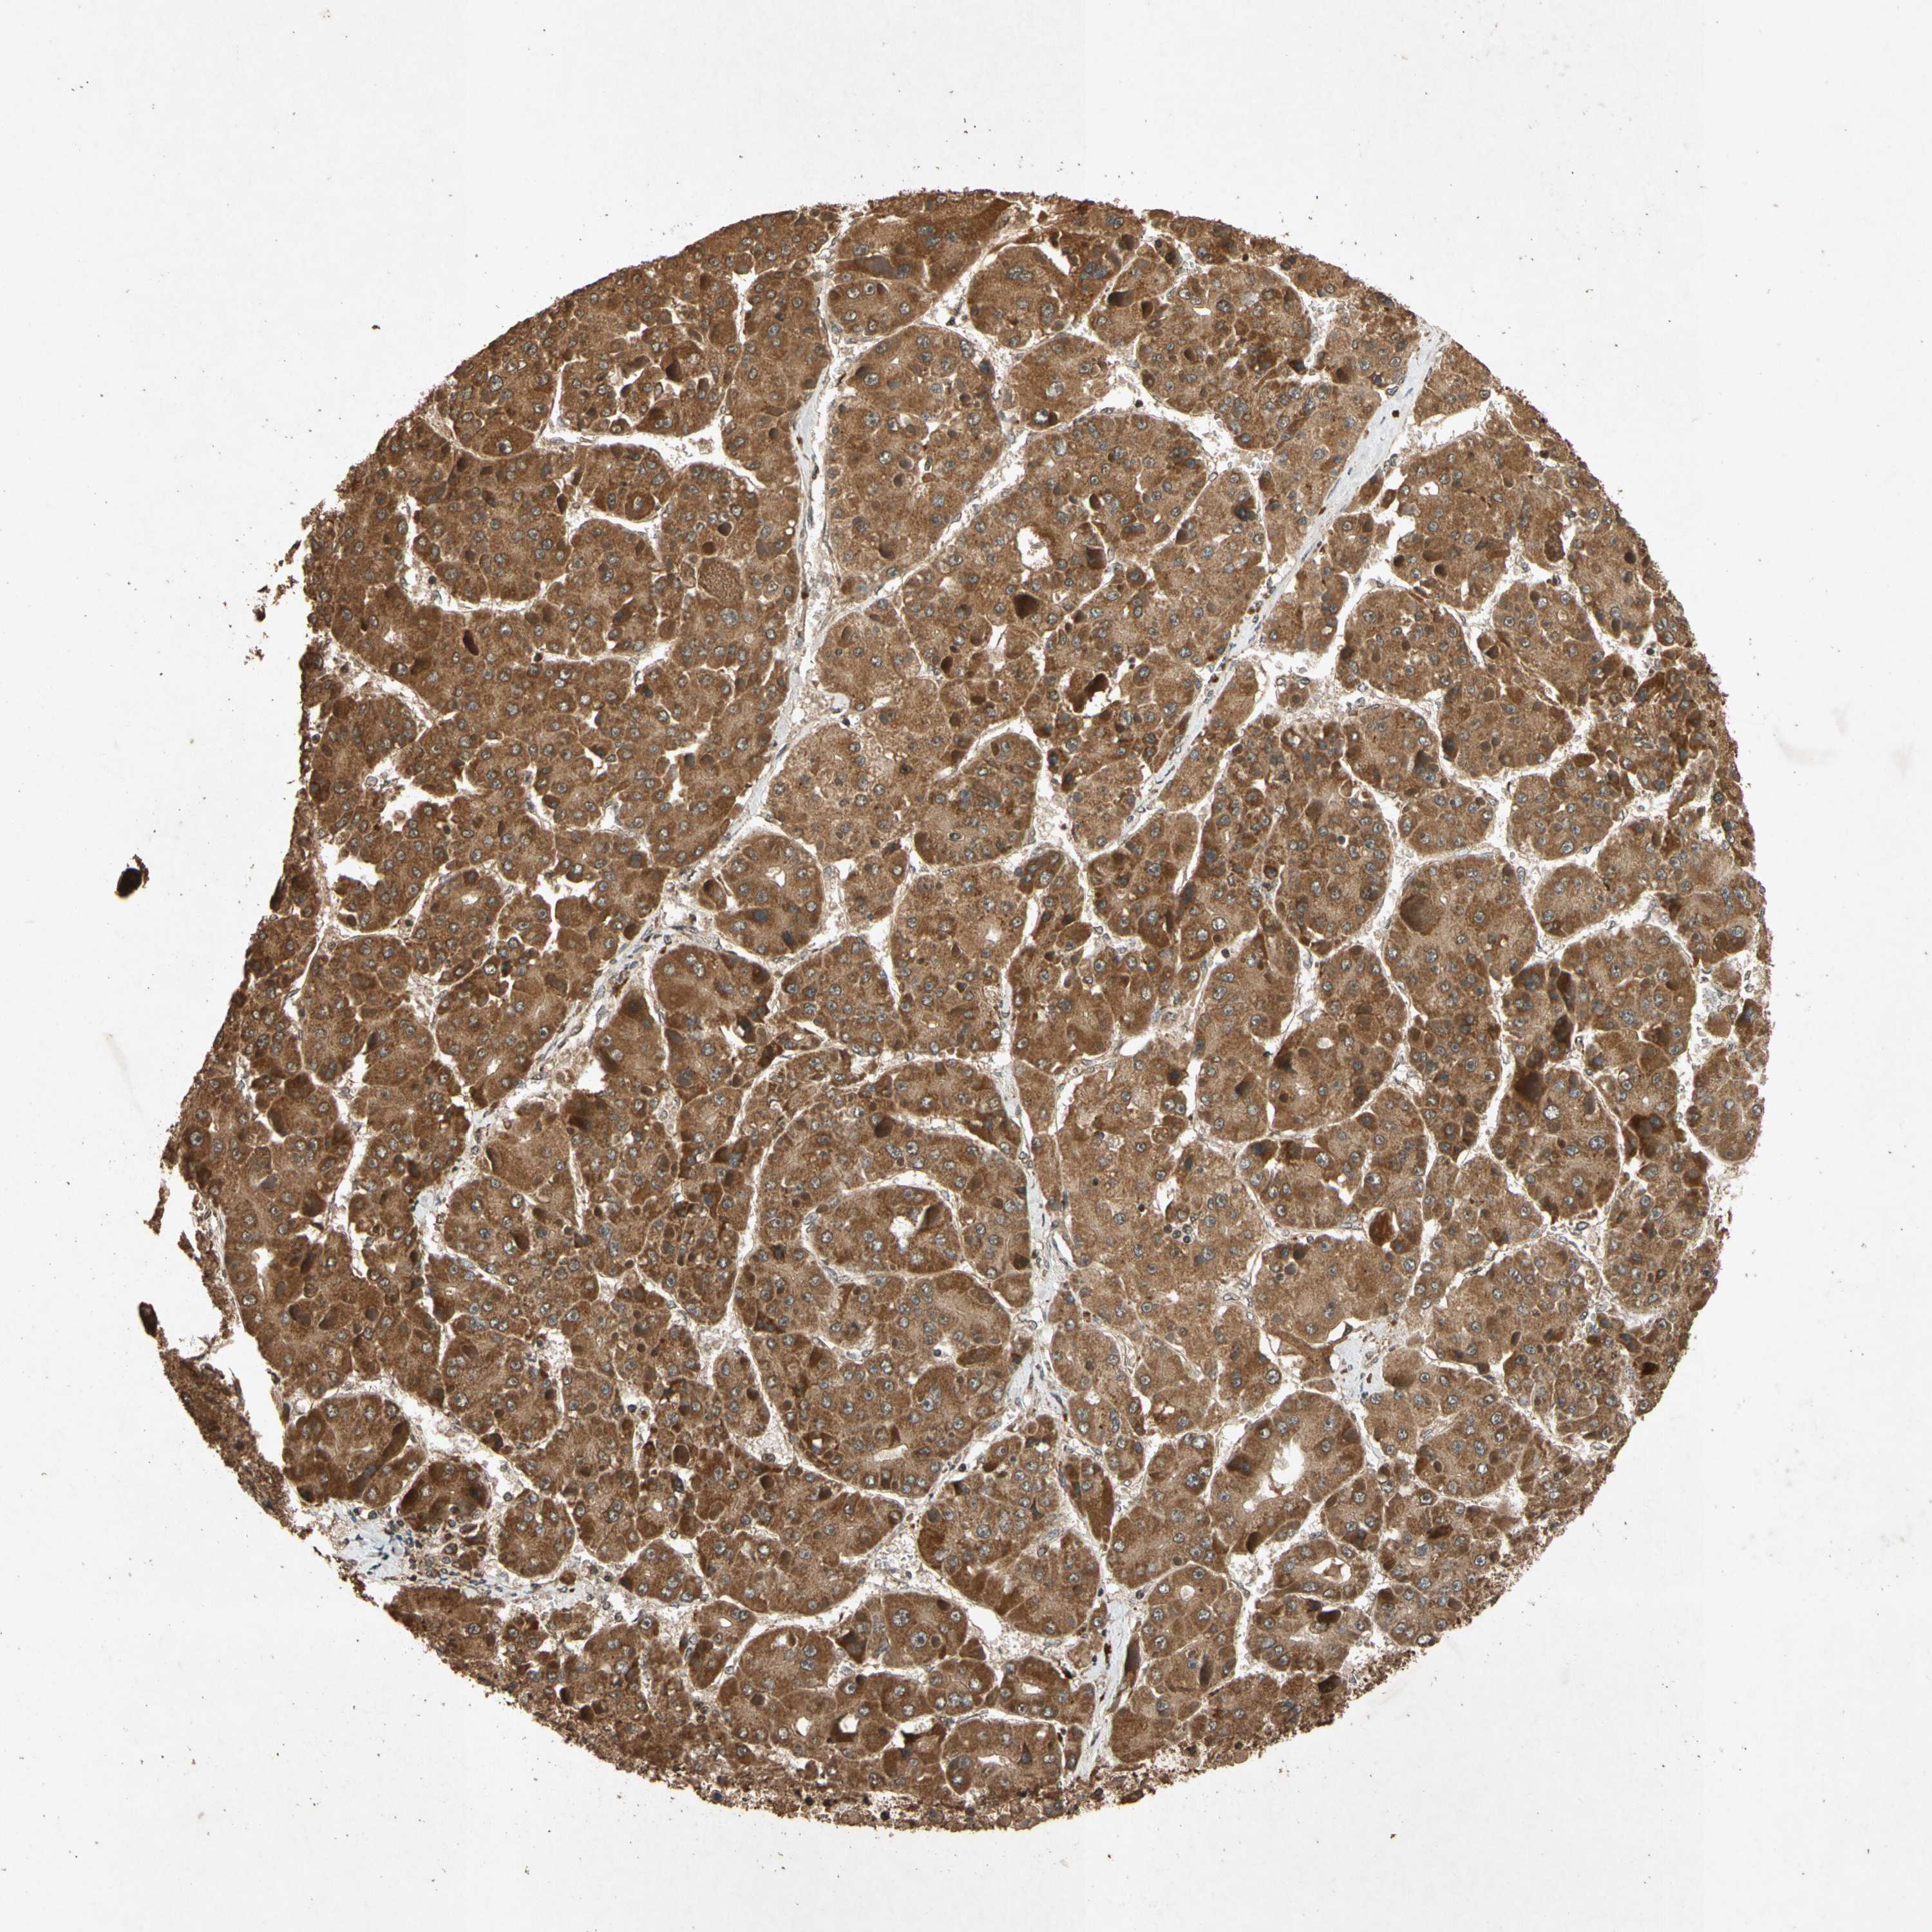

LIVER CANCER - Protein expressioni

A mouse-over function shows sample information and annotation data. Click on an image to view it in a full screen mode. Samples can be filtered based on level of antibody staining by selecting one or several of the following categories: high, medium, low and not detected. The assay and annotation is described here.

Note that samples used for immunohistochemistry by the Human Protein Atlas do not correspond to samples in the TCGA dataset.

Antibody stainingi

Antibody staining in the annotated cell types in the current human tissue is reported as not detected, low, medium, or high, based on conventional immunohistochemistry profiling in selected tissues. This score is based on the combination of the staining intensity and fraction of stained cells.

Each image is clickable and will lead to virtual microscopy that enables deeper exploration of all samples and also displays staining intensity scores, fraction scores and subcellular localization as well as patient and tissue information for each sample.

Antibody HPA000994

Antibody CAB008681

Staining

High

Medium

Low

Not detected

Intensity

Strong

Moderate

Weak

Negative

Quantity

>75%

75%-25%

<25%

None

Location

Nuclear

Cytoplasmic/membranous

Cytoplasmic/membranous,nuclear

Carcinoma, Hepatocellular, NOS

Cholangiocarcinoma